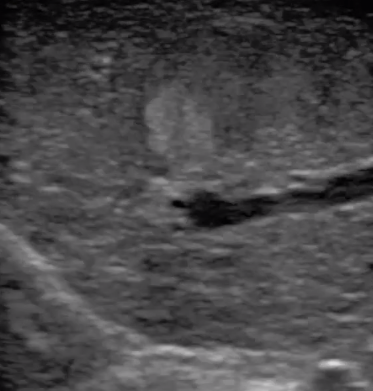

腹腔鏡超聲是超聲技術(shù)和腹腔鏡技術(shù)的融合,腹腔鏡超聲降低了對(duì)超聲探測(cè)深度的要求。由微小切口進(jìn)入手術(shù)部位,多角度彎曲可選擇,降低手術(shù)難度及風(fēng)險(xiǎn);與受檢組織器官直接接觸,有效避免氣體干擾。

應(yīng)用科室:麻醉科、手術(shù)室、普外科、泌尿外科、婦產(chǎn)科、腫瘤科、介入科等

腹腔鏡下 肝臟占位